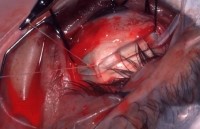

4. Encircling procedure

5-0 ethibond 로 suture (cvd needle)

->suture한 부위에 silicone tube 506의 끝을 뾰족하게 scs로 자른 후 넣는다.

(미리 silicone tube 506은 GM bss 용액에 담아 놓는다)

->SB Set내에 있는 ㄱ자 fcp으로 insertion

->cut scs: wescott , retractor: 주걱모양

assist 의 손이 부족 하기 때문에 주걱모양 retractor 사용시 도움이 필요

교수님께서 suture할 때 black silk 당긴 채 suture

5.close

conjuctiva suture : 8-0 vicryl

->gas injection

->안연고

->medress